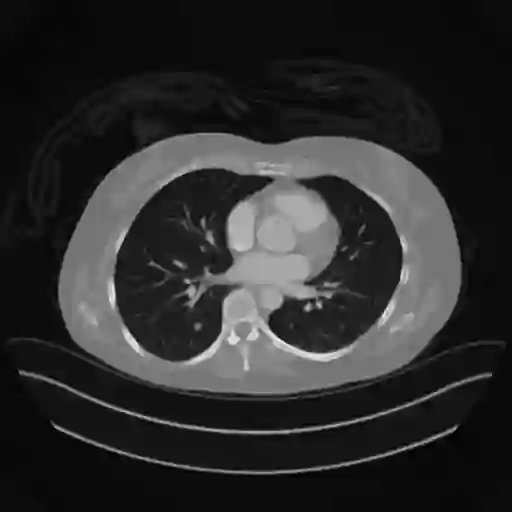

Sparse-view computed tomography (CT) -- using a small number of projections for tomographic reconstruction -- enables much lower radiation dose to patients and accelerated data acquisition. The reconstructed images, however, suffer from strong artifacts, greatly limiting their diagnostic value. Current trends for sparse-view CT turn to the raw data for better information recovery. The resultant dual-domain methods, nonetheless, suffer from secondary artifacts, especially in ultra-sparse view scenarios, and their generalization to other scanners/protocols is greatly limited. A crucial question arises: have the image post-processing methods reached the limit? Our answer is not yet. In this paper, we stick to image post-processing methods due to great flexibility and propose global representation (GloRe) distillation framework for sparse-view CT, termed GloReDi. First, we propose to learn GloRe with Fourier convolution, so each element in GloRe has an image-wide receptive field. Second, unlike methods that only use the full-view images for supervision, we propose to distill GloRe from intermediate-view reconstructed images that are readily available but not explored in previous literature. The success of GloRe distillation is attributed to two key components: representation directional distillation to align the GloRe directions, and band-pass-specific contrastive distillation to gain clinically important details. Extensive experiments demonstrate the superiority of the proposed GloReDi over the state-of-the-art methods, including dual-domain ones. The source code is available at https://github.com/longzilicart/GloReDi.